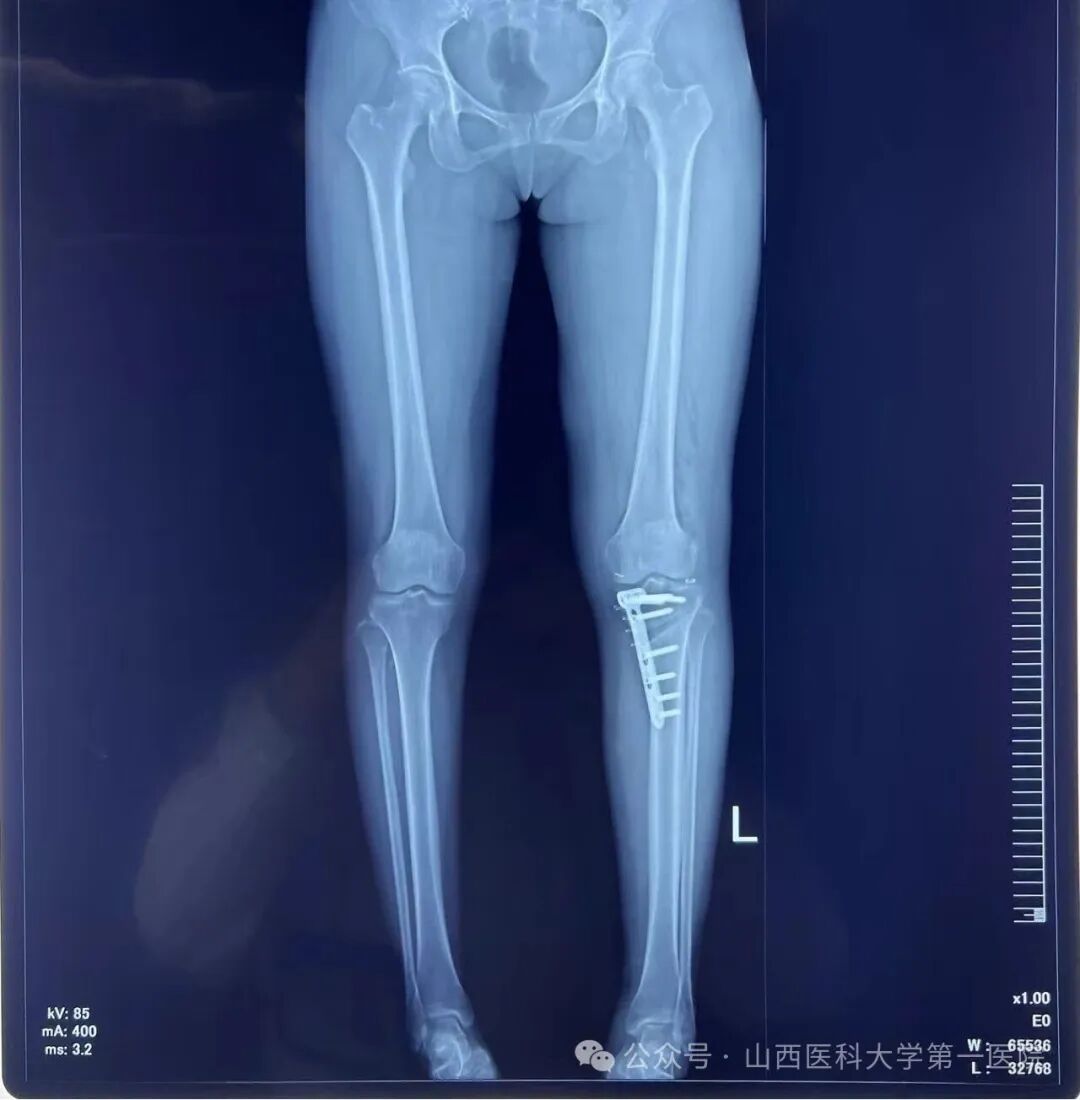

放置钢板后行X线确认位置满意

术后左下肢力线明显矫正

此次手术患者的膝关节核磁显示半月板有明显的撕裂,因此单纯行HTO无法解决半月板损伤的问题。骨科主任杨自权作为山西省运动医学的领军人物,运用关节镜为患者解决半月板损伤的问题,同时在AI设计的3D-PSI的辅助下实施精确地截骨矫正下肢机械轴力线,从而达到令人满意的手术效果。